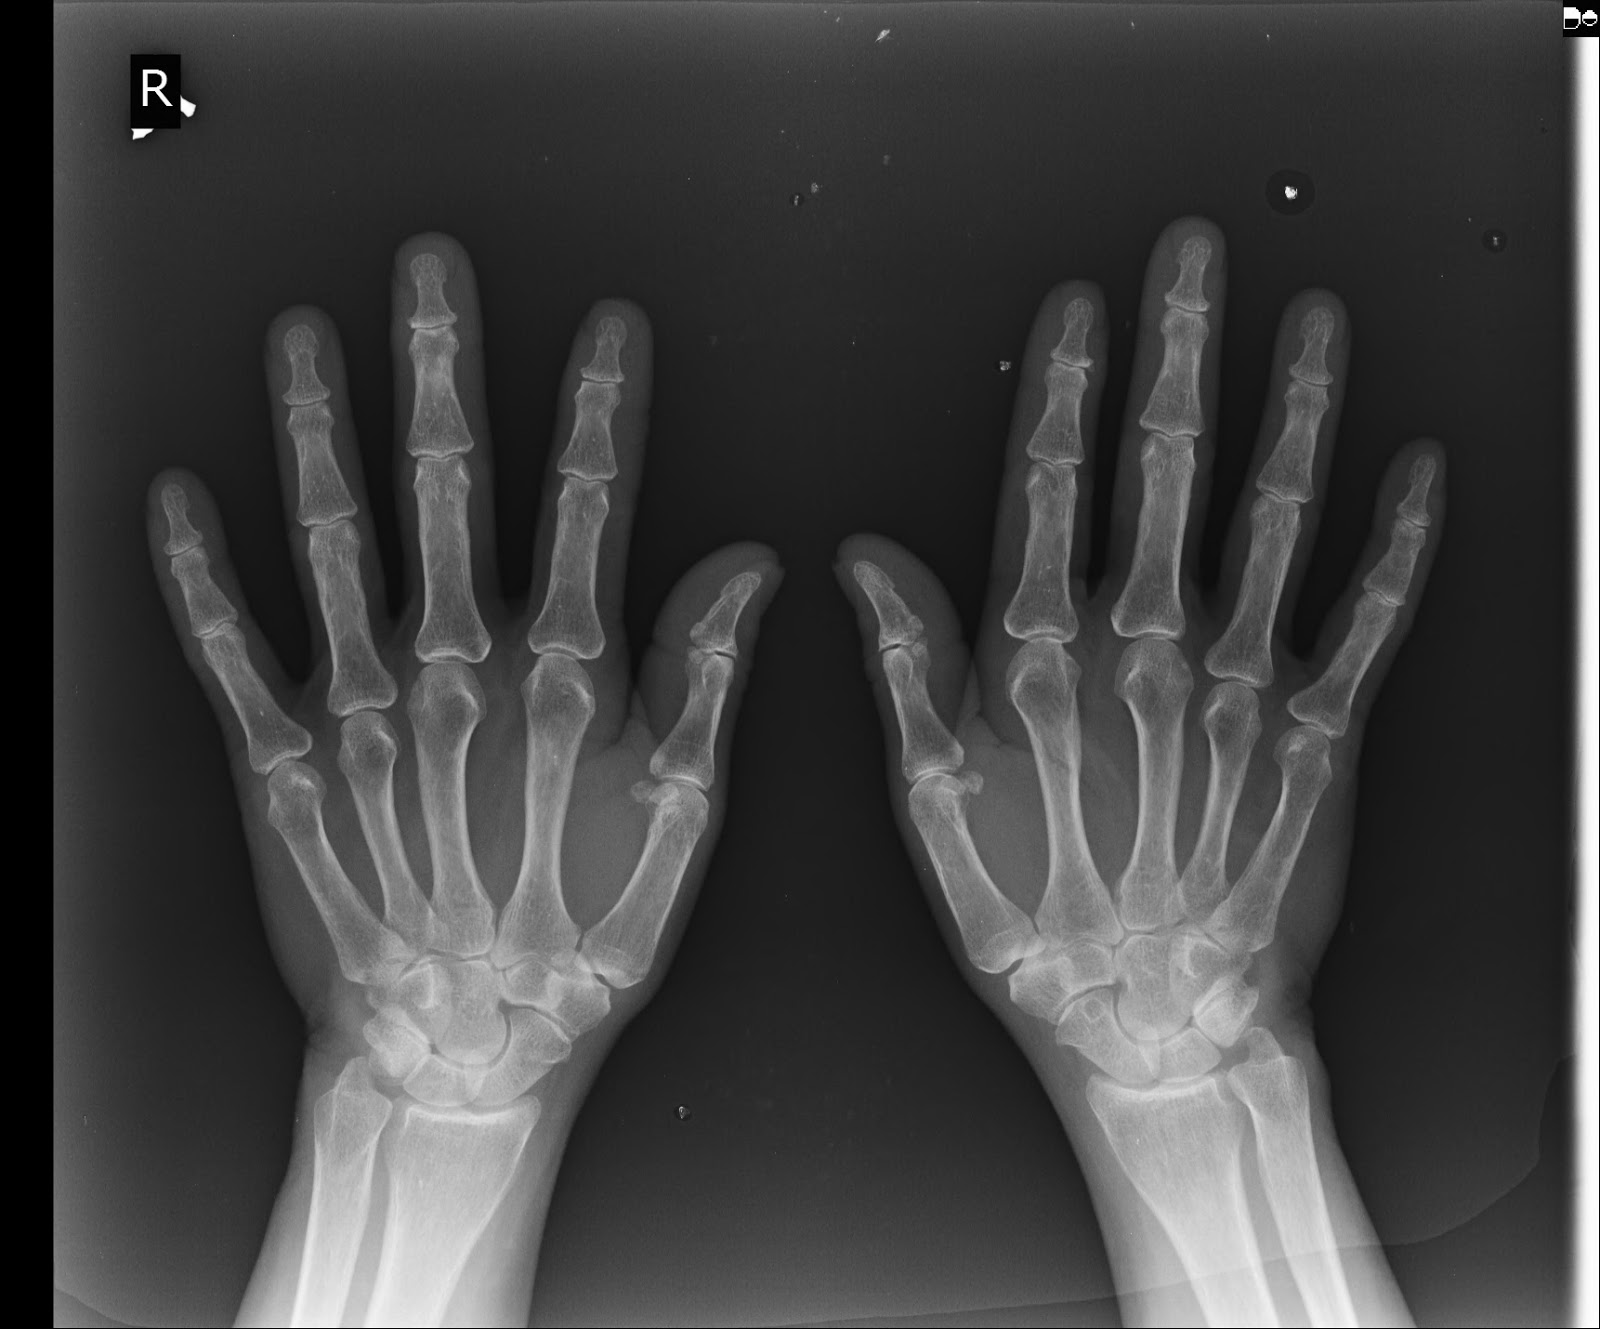

Radiology of CALOTROPIS464PROCERA(MR),,A 60 year old woman suffering from OA bilateral knee, left Carpal tunnel syndrome & left cervical neural foraminal syndrome since 4 month..

X-ray hands